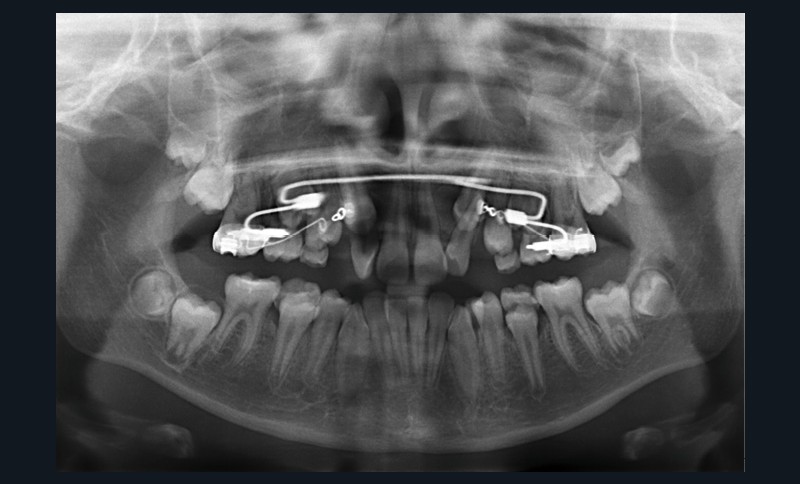

Un appareil multi-attache est mis en place avec une prescription MBT en .022 x .028. une fois les faces vestibulaires des canines maxillaires apparentes. 13 et 23 ne sont pas prises en charge dans l’arc pour éviter les effets parasites sur les dents adjacentes. Leur traction est poursuivie avec des élastiques de Classe II (1/4” – 3.5 oz) en port nocturne. Ces élastiques sont portés sur un bouton palatin pour la 23 afin de corriger sa rotation mésio-vestibulaire. Une fois les canines suffisamment proches du plan occlusal, elles sont prises en charge dans un arc continu en suivant les séquences suivantes : .014, .018 et .019 x .025 Niti. Une fois l’arc .019 x .025 en Niti en place pendant huit semaines, l’arc transpalatin est déposé. L’arcade mandibulaire suit cette même séquence d’arcs avec l’ajout d’un arc en acier .019 x .025 avec courbe de Spee inversée pour aider à la correction de la supraclusion.

À ce stade, une radiographie panoramique est réalisée pour s’assurer de l’intégrité des racines, contrôler les axes dentaires et planifier le repositionnement de certaines attaches ainsi que le collage des tubes sur les secondes molaires en cours d’éruption.

Un arc acier .019 x .025 est inséré à l’arcade maxillaire et les finitions sont réalisées sur des arcs en TMA .017 x .025.

L’appareil est déposé après la mise en place de contentions collées de 12 à 22 et de 33 à 43 avec le port nocturne d’une plaque de Hawley à l’arcade maxillaire. Le temps de traitement actif a été de 41 mois.